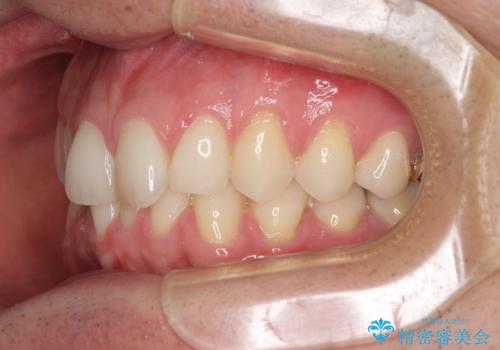

ディープバイトと叢生 インビザラインによる矯正治療

- 前歯のディープバイトと叢生を気にして来院された患者様です。

目立ちにくい装置を希望されていたため、ワイヤー装置とインビザラインを提案したところ、インビザラインを希望されました。

上下ともに叢生が認められたため、親知らずすべてを抜歯し、歯列全体を後方へ移動させることで歯列を整えることとしました。

上顎奥歯の銀歯も気になっていたので、矯正治療の途中でセラミッククラウンへ変更し、その後歯列を仕上げていくこととしました。

ディープバイトもデコボコも改善され、気になっていた銀歯もセラミックとなり、患者様には大変満足していただきました。